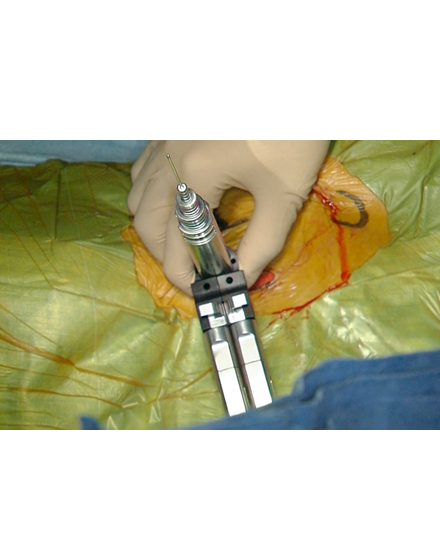

骨粗鬆症による背骨の骨折や転移性脊椎腫瘍(がんの背骨への転移)による病的骨折に対して世界中で行われている低侵襲な手術法です。日本では2011年に保険適用になり行われています。全身麻酔をして背中の約5mmの傷2カ所から細い針を骨折椎体に挿入します。その針を介して風船(Balloon)を骨折椎体内に設置し、ゆっくりと潰れた骨を整復・復元します。整復後に除去した風船のスペースに骨セメントを注入して、骨折を人工的に接合します。手術は約1時間程度で、手術直後から痛みが軽減することが多く、翌日より起立・歩行を開始します。入院期間は通常約3~7日程度になります。